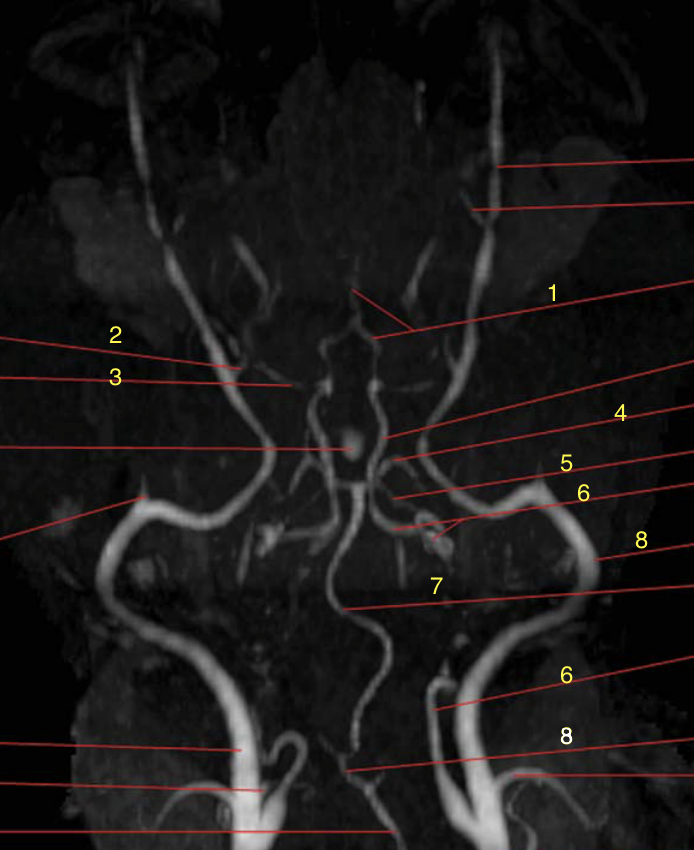

Label the vasculature

Is 3D FLASH or 3D TOF better to visualie the cerebral arterial circle (Circle of Willis)?

TOF is better to visualize the cerebral arterial circle (arteries as small as 0.4mm)